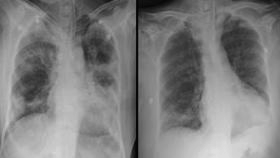

혈장치료 첫번째 완치사례는 71세 남성분이에요. 이 분은 열과 기침 증상을 보이다가 코로나판정을 받았는데요. 이후 병원에서 다양한 바이러스제 치료를 받았지만, 폐렴증상이 호전되지 않아 세브란스 병원으로 옮겨졌답니다.

당시 호흡속도는 정상인보다 높았으며, 흉부검사에서도 양쪽 폐 모두 심각한 증상을 보였기에 세브란스병원에서는 기계호흡을 시작했다고해요.

치료결과 이틀후부터 산소요구량 감소, CRP(C-반응성단백질)수치가 떨어졌으며 기계호흡을 끊고 자발적인 호흡을 회복하고 음성판정을 받고 완치가 되었답니다.

두번째 완치사례는 67세 여성분이에요. 이 분은 고열과 근육통으로 진단을 받은 후 3일째부터 호흡곤란으로 산소요구량이 많아지면서 왼쪽 폐 상태가 나빠져 세브란스병원으로 이송되었답니다.

이송당시 호흡속도는 정상인보다 조금 높았으나, 산소포화도는 정상인보다 낮아서 호흡곤란증세가 심각했다고 해요.

흉부검사에서도 폐의 침윤이 좋아지고 CRP 역시 정상수준으로 회복을 하게 되면서 완치판정을 받고 퇴원을 하게 되었답니다.